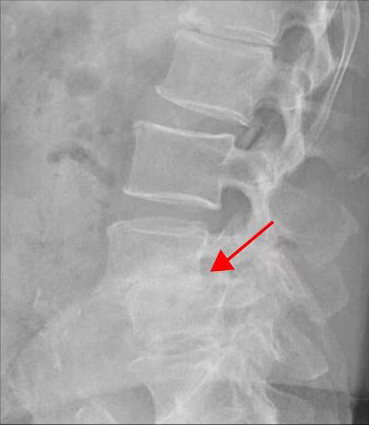

<4-5번 추간공협착증>

<4-5번 척추전방전위증>

이 환자분은 요추 4-5번 오른쪽에 심한 추간공협착증, 2단계의 전방전위증이 있으며, 특히 전방전위증으로 인해 추간공이 매우 좁아져 있습니다. 또 요추 5-1번 왼쪽에 디스크 파열이 있습니다.